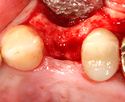

يتم اجراء جراحة الأسنان في العيادة تحت ظروف معقمة، من قبل طبيب أسنان متخصص في زراعة الأسنان و/أو جراحة الفم والفك. يتم تخدير المريض بواسطة حقنة بمخدر موضعي في منطقة دواعم السن، كما هو الحال في علاجات الأسنان العادية (في بعض الأحيان هناك حاجة بتوسيع نطاق التخدير، وفقاً لموقع الغرسات).

اذا كان العظم على استعداد لتلقي الزرع (أحيانا بعد سلسلة علاجات مسبقة)، يمكن البدء بعملية زرع الاسنان. يتم تثبيت المسامير المعدنية اللولبيه براغي، بعظم الفك. في سلسلة اخرى من العلاجات بعد فترة من ادخال البراغي، تبدا عمليات اعادة البناء عن طريق أخذ القياسات وانشاء التاج/الجسر. عندما يدور الحديث عن فترة الانتظار بين تركيب الغرسات وبين تنفيذ الاستبناء النهائي، فان هنالك اكثر من نهج واحد. النهج المتبع غالبا هو الانتظار لمدة 6 أسابيع على الأقل حتى تلتئم الانسجة، وأحيانا تصل فترة الانتظار لعدة شهور.